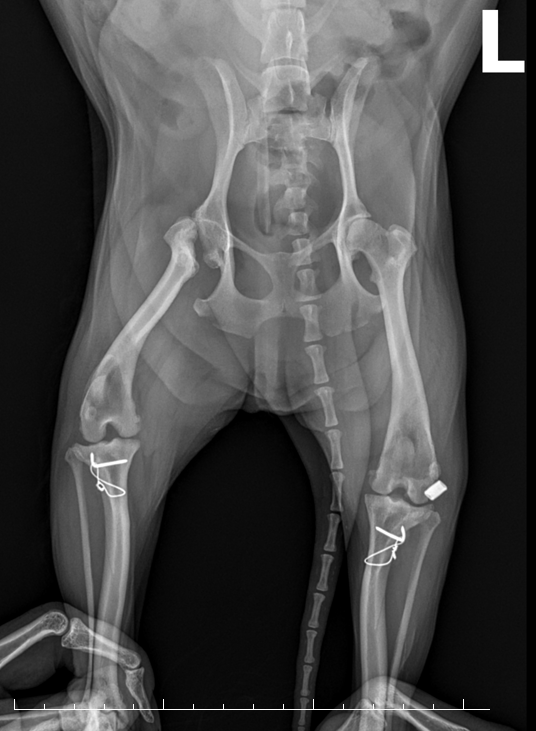

02X-ray 검사무릎 관절을 체크하고,십자인대 단열을 확인합니다.

TPLO 십자인대 수술절뚝거리는 증상으로 내원!

TPLO 수술 후 건강한 일상으로 복귀 -

MPL, TPLO 슬개골 탈구 + 십자인대슬개골 탈구 수술과 십자인대 수술

동시 진행 케이스